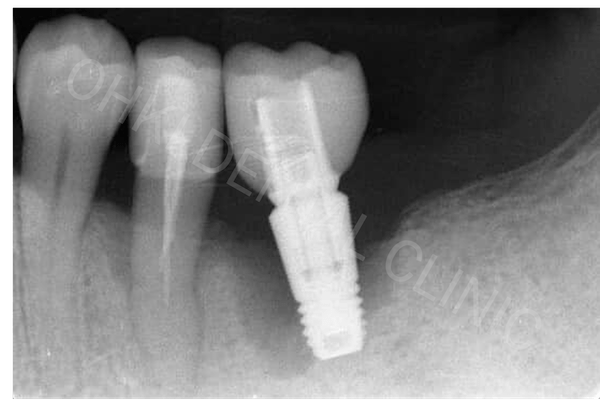

歯肉炎と歯周炎(歯槽膿漏)の違いは「歯を支えている顎の骨が溶けているか」で判断をしています。

そのため歯周病の診断には歯周ポケットの深さや出血の有無を測定する歯周基本検査だけでなく、レントゲン写真で骨の状態も確認しながら診断をします。

歯周病の問題が残った状態でのインプラント治療は、治療自体はできなくもないですが、インプラントの耐久年数に影響が出てくる可能性があります。

インプラントは人工歯根を顎の骨の中に埋入して歯を作る治療なので、歯周病によって歯を支えている顎の骨が溶けてしまうとご自身の歯同様にインプラントも抜けてしまいます。

歯周病(歯槽膿漏)が進み重症化すると、インプラントを埋入するための必要な量の骨が溶けてなくなっている場合があります。

また今は重症化していなくても、歯茎の腫れや出血が続いている状態でのインプラント治療は長持ちしないリスクが高くなります。